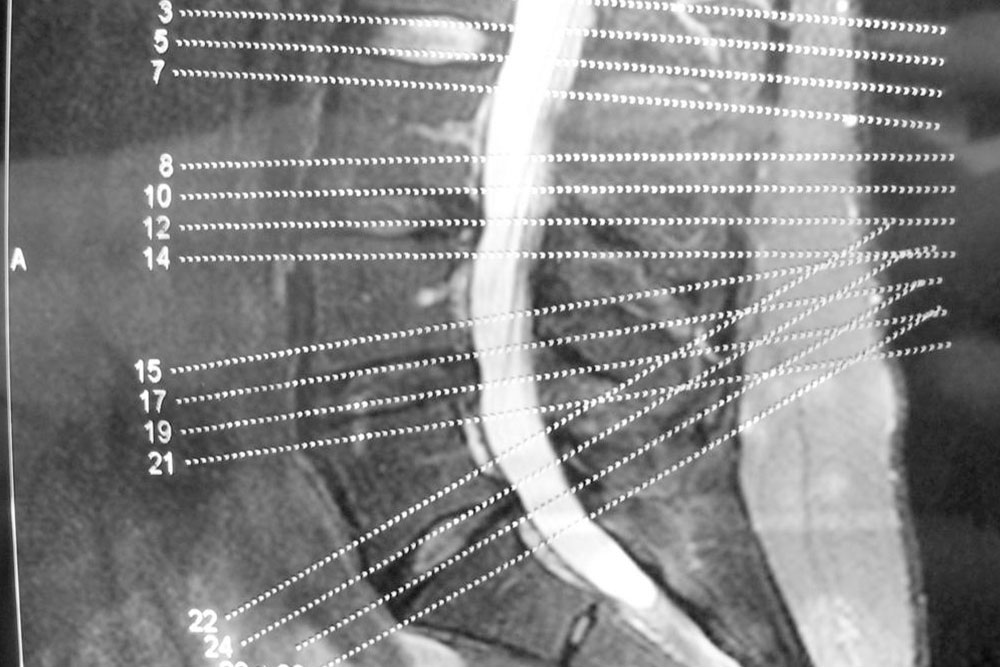

Degenerative Disc Disease

The spinal column consists of spinal discs that perform the task of providing padding between the vertebrae, i.e., the series of small bones that make up our backbone. They also act as shock absorbers and help the back remain flexible. As we age, these discs start gradually losing their elasticity property.

A common cause of this condition is the drying of your spinal discs. As you age, the water in the spinal discs dries out, flattening the spinal disc. A flattened spinal disc cannot absorb shock and they fail to provide padding to the vertebrae. Another cause of this disease can be a crack in the spinal disc. If the walls of the disc tear out, then there is a high chance that the soft core of the disc might push through the cracks and cause the disc to swell or, in the worst case, slip off.

Degenerative Joint Disease

Commonly referred to as Osteoarthritis, the degenerative joint disease is caused by the wearing of the body tissues. One of the most commonly affected areas is the joints in the spine.

This disease affects the facet joints, which are the joints that protect the vertebra in the spinal column from both sides. These joints make it possible for the spine to bend effortlessly.

The facet joints are lined with cartilages that cushion the joint and make sure that two adjacent vertebrae can glide smoothly against one another.